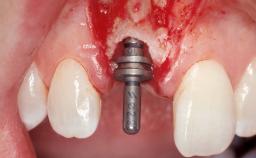

| # of Implants | 1 |

| Type of Implants | Two-Piece |

| Placement Protocol | Early or late implant placement |

| Bone Volume | Deficient horizontally, requiring prior grafting |